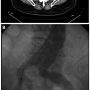

After baseline angiography and positioning of an 0.35 Amplatz Superstiff wire (Boston Scientific) in the aortic arch, an 28 x 140 cm Gore Excluder EVG body (W. L. Gore & Associates) (Figures 1 and 2) was deployed immediately below the lower renal artery. Then, controlateral gate was cannulated by means of a 260 cm 0.035-inch Radifocus wire (Terumo) and a multipurpose (Cordis). The Radifocus wire was exchanged for an Amplatz Superstiff wire and a 18 Fr sheath was carefully advanced to reach the gate region for contralateral deployment of a 18 x 10 cm leg.

During this maneuver, the dilator of the sheath touched the entrance zone of the gate and dislodged the EVG moving it proximally in the thoraco-abdominal aortic segment causing complete occlusion of both renal arteries and celiac trunk (Figure 3). Despite careful sheath advancement under fluoroscopy guidance, the migration was so rapid that it could not be prevented by sheath retraction. A Radifocus wire was then advanced in the EVG body and by the means of a Simmons 1 catheter (Cordis) the contralateral leg was engaged in a cross-over fashion. A goose-neck 35 mm catheter (Cook) was then advanced from the left femoral artery enabling the capture of the Radifocus wire, whose tip was then